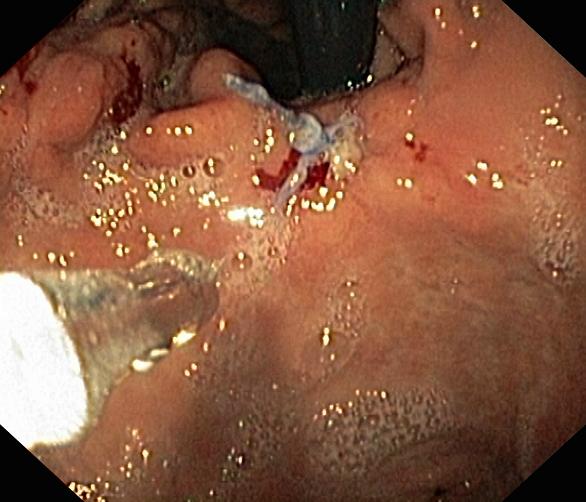

Krwawienie